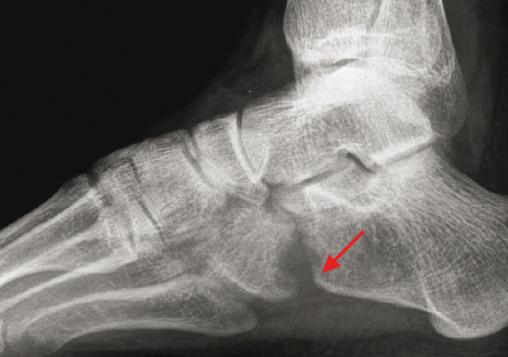

Radiographie de profil du pied : arthrite tuberculeuse calcanéo-cuboïdienne (élargissement de l'interligne lié à la destruction de l'os sous-chondral).